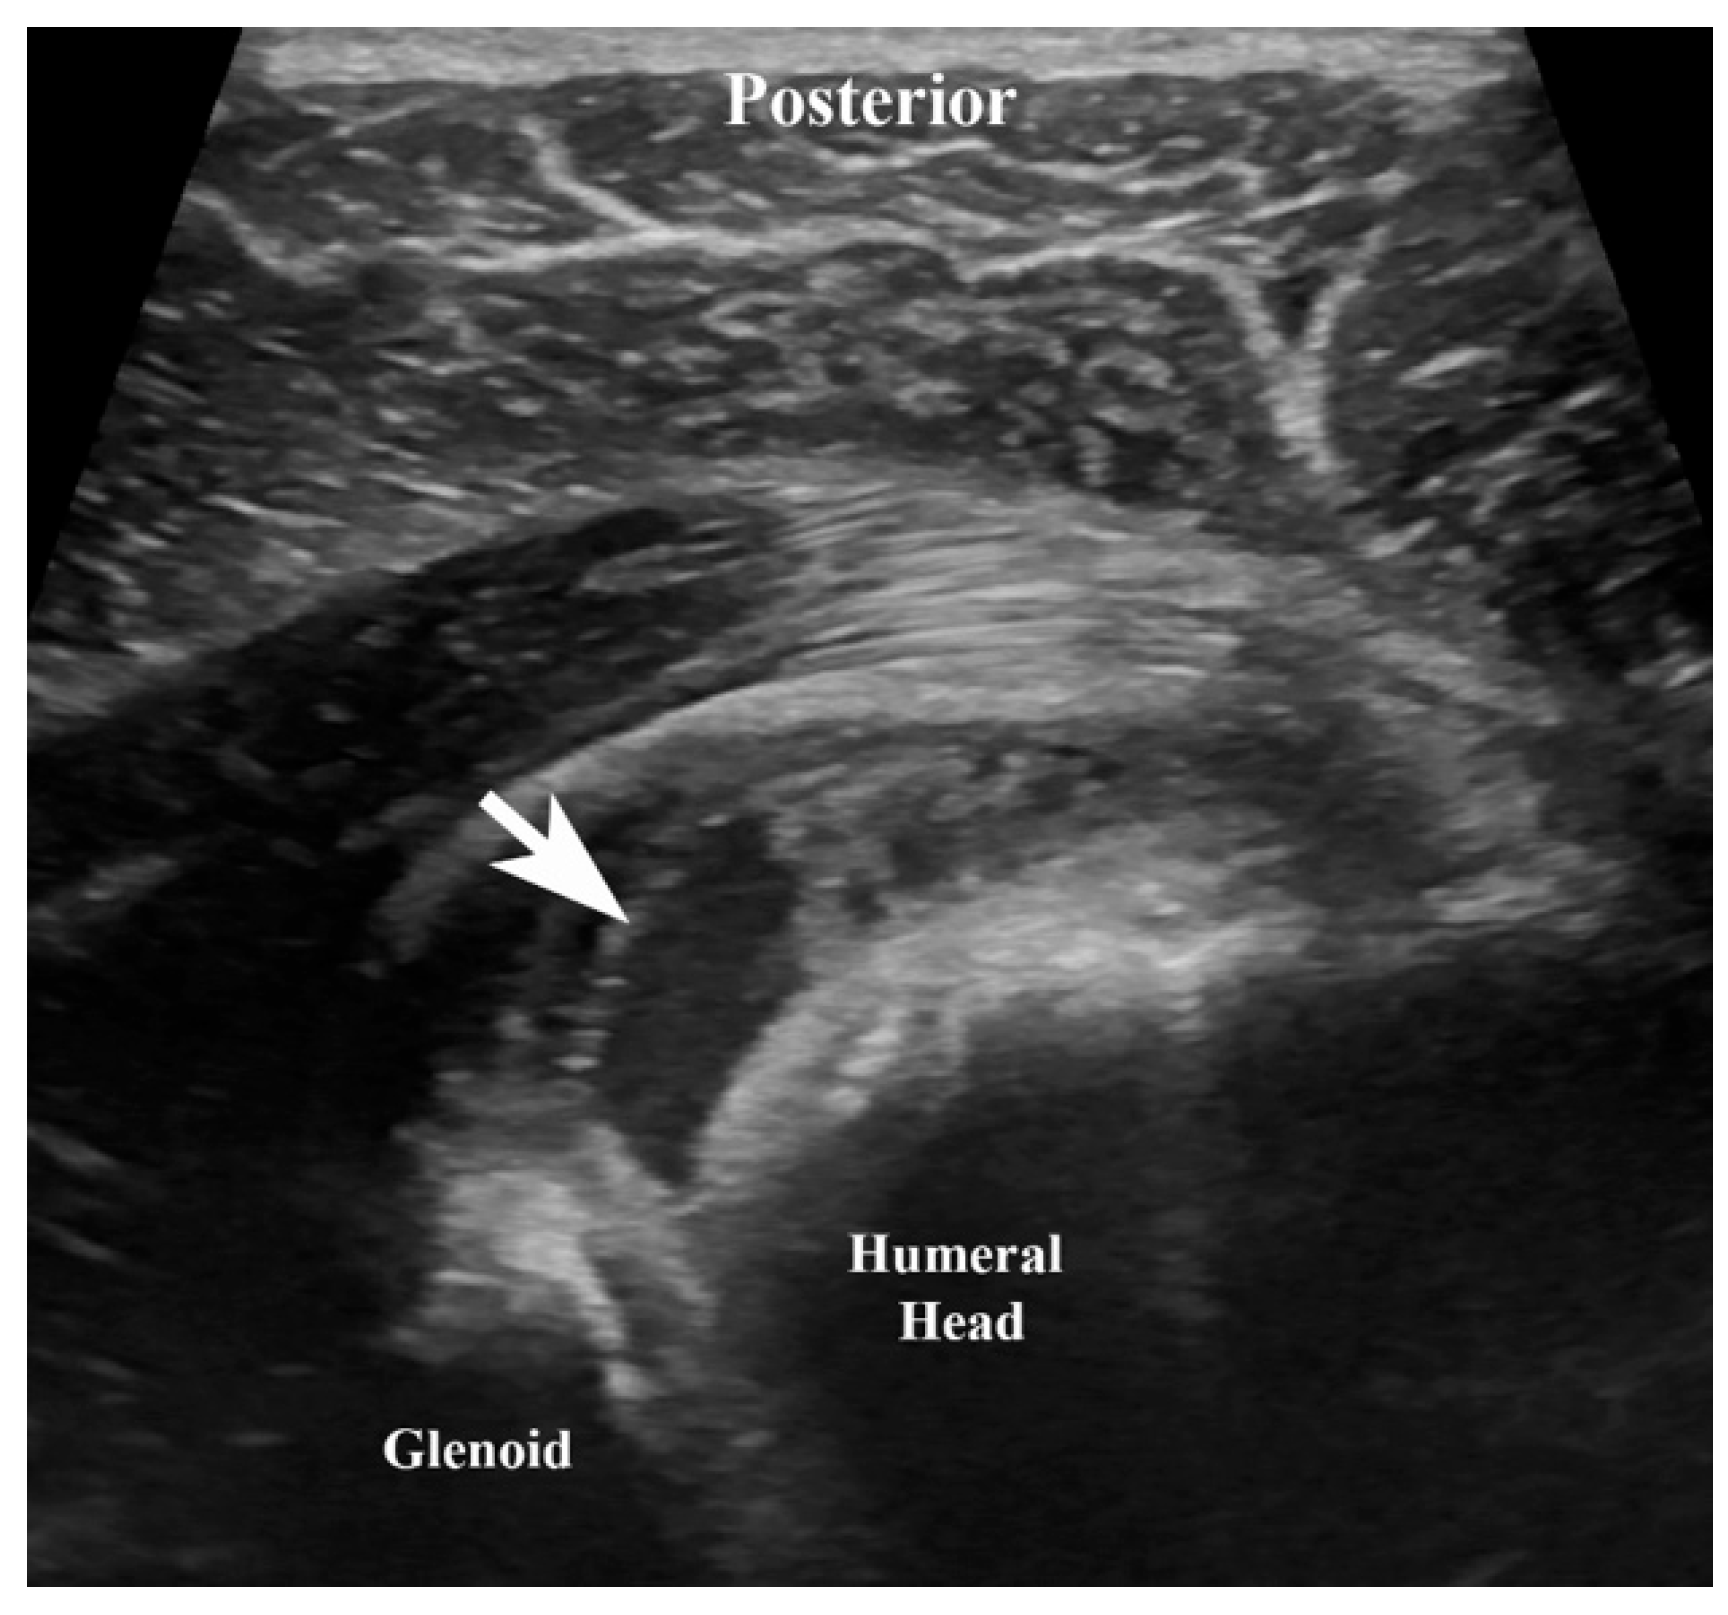

| 2 December | 9 | Ultrasound-guided arthrocentesis of the right shoulder performed; synovial fluid cultures grew Salmonella species. |